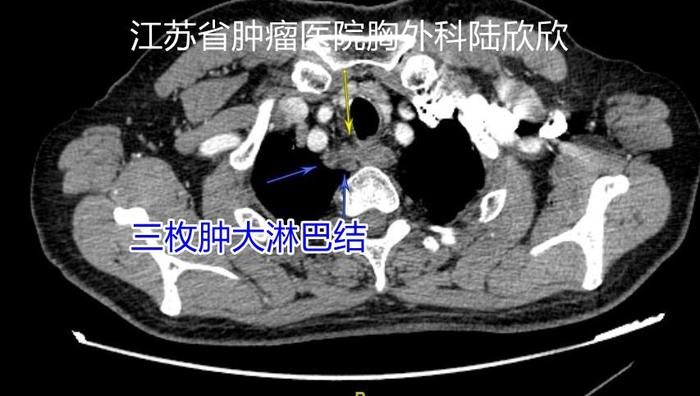

术前和家属说:肿瘤巨大,外侵明显,手术非常困难。肿瘤巨大,目前起码还有右气管食管沟三枚淋巴结转移,恶性度很高。理论上最好新辅助化疗等治疗让肿瘤缩小一些,再进行手术治疗,这样手术难度小一些,手术风险小一些。但是,术前新辅助治疗也有缺点。假设肿瘤在术前新辅助治疗以后,不仅不缩小,反而增大,那么将丧失手术机会。谁也不能保证肿瘤治疗后一定缩小。第二个缺点,肿瘤溃疡很深,一旦肿瘤的溃疡穿孔,到时候急诊手术治疗癌性穿孔,这时手术的死亡率会升高几十倍,手术死亡率要超过50%。现在手术,也有可能出现肿瘤切除不掉,或者大出血死亡在手术台上。

三枚增大的右气管食管沟淋巴结,位于脊柱右前方,从右边手术较为容易,这次手术从左边手术难度较大。淋巴结旁边有喉返神经。术后声音嘶哑与切除这几个淋巴结有关。